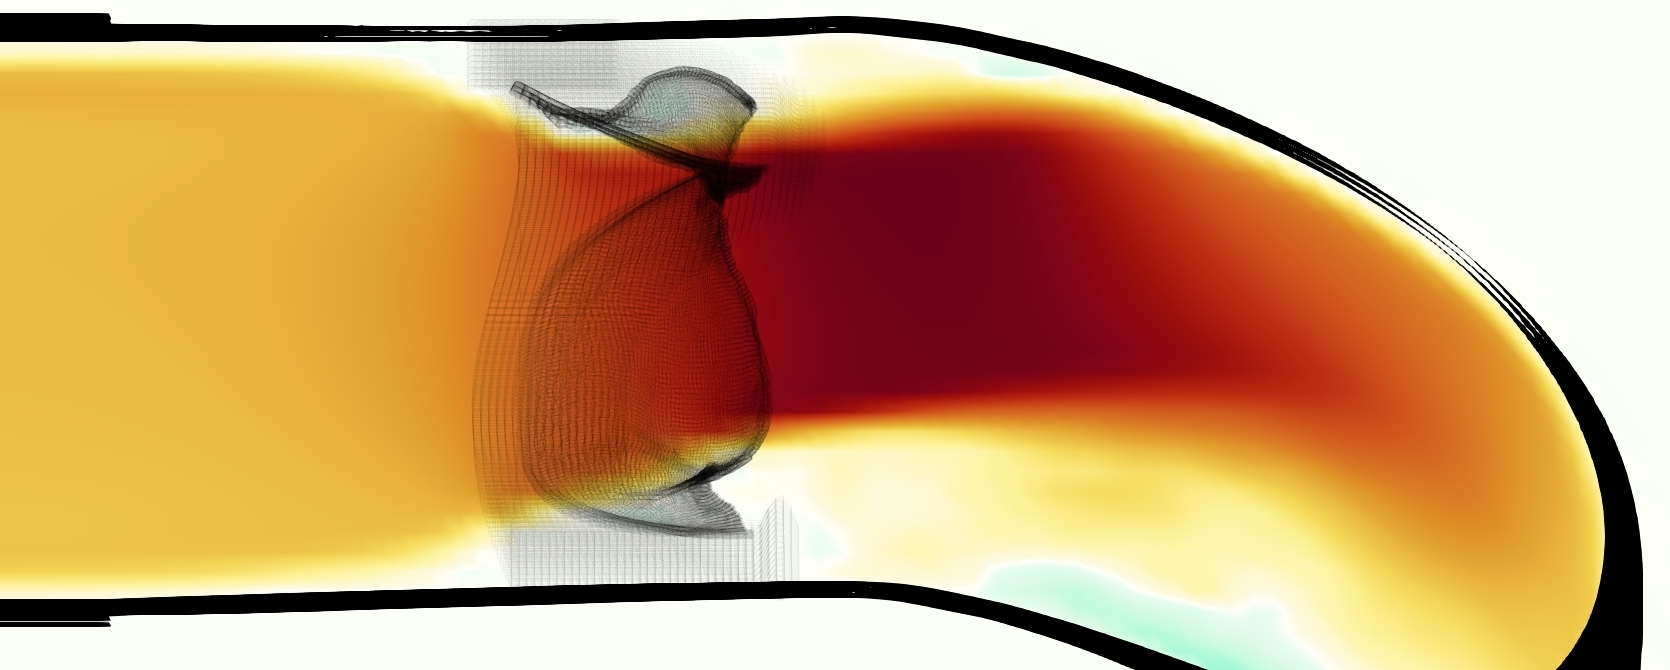

The emergent hemodynamics showed excellent qualitative agreement with experiments. Slice views of the axial component of fluid velocity ( component) in the sagittal plane that cuts through the center of the vessel, parallel to the flow direction, are shown in Figure 5. The flow in both the simulation and the experiment began to accelerate at the same time, with a jet forming through the open valve leaflets. The velocity, angle, and shape of the jet agreed well between the two cases during systole. The simulation captured the slight upward angle of the jet, which was not fully centered in the vessel. It also matched the location where the jet impacts the wall and the slower speed of the jet as it turns with the MPA downstream. As the flow decelerated, the fluid along the interior curve of the vessel reversed first while forward flow persisted where the jet was strongest, as seen in both the simulation and experimental results.

In both the experiment and the simulation, a separation region of reverse flow developed along the interior curve of the vessel under the core jet through the valve. The reverse flow began to develop at the same time in the cardiac cycle and grows throughout systole. The simulation lacked reversed flow in the entire region where reversed flow was present in the experiment, but this region developed some flow separation and had much slower flow than elsewhere in the vessel. Thus, the simulation captured that this is a distinct region from the core jet through the valve opening. There was a smaller amount of slower and slightly reversed flow along the outer curve of the vessel, close to the valve annulus and scaffold support. This region was well-matched between the experiment and the simulation.

A comparison between the phase-averaged velocity resampled onto the MRI grid, the phase-averaged velocity without resampling, the instantaneous flow field without resampling and the MRI velocity field is shown in Figure 8. The coarser resolution is visible as a “stair-stepping” or “pixelated” effect on the phase-averaged resampled velocity, whereas the edges of the jet are more smooth in the phase-averaged velocity with no resampling. Otherwise, the resampled velocity appears qualitatively similar to the phase-averaged velocity with no resampling. Fine scale features were present in the instantaneous field that were lost in the phase-averaging and resampling process. There was more variation in the local velocity of the center of the jet and local areas of high velocity at the edges of the jet that suggested vortices. Vortical structures adjacent to the jet and in the areas of reversed flow were apparent. These comparisons suggest that 4D flow MRI data may lose substantial fine-scale flow features in the flow field via phase-averaging.